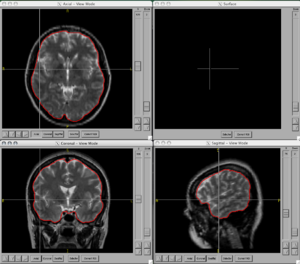

BRAINSCut is a software package for segmentation of structures using artificial neural networks. Currently this tool supports the segmentation of the following structures: brain, caudate, putamen, thalamus, hippocampus, anterior cerebellum, interior posterior cerebellum, superior posterior cerebellum, corpus medullary. Future regions will include the globus pallidus, amygdala, and nucleus accumbens. The command line uses the Slicer3 execution model framework.

Figures

- BRAINSCut